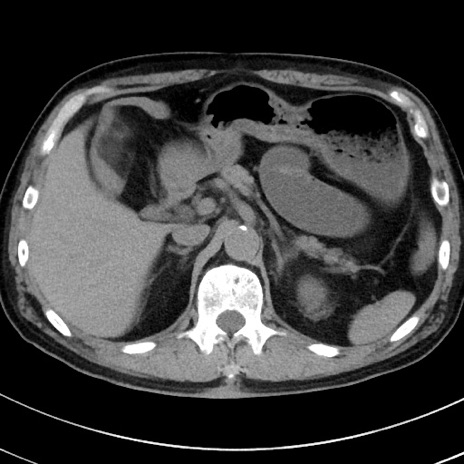

症例38(横断像)

【症例】70歳代 男性

【主訴】腹痛・嘔吐

【現病歴】昨晩より、嘔吐・腹痛あり。今朝になっても嘔吐あり。来院。

【既往歴】心臓バイパス手術、開腹胆摘、腸閉塞

【身体所見】BP 107/71mmHg、HR 116/min、腹部:平坦、軟、下腹部に軽度圧痛あり。反跳痛なし。

【データ】WBC 15100、CRP 0.32